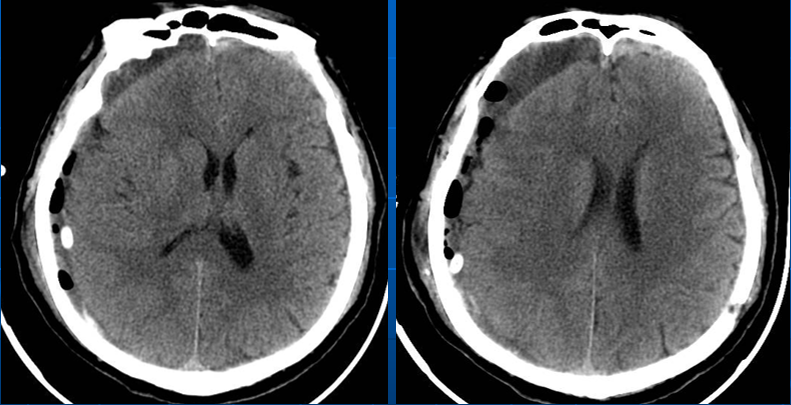

术后情况

术后当日(2019年1月16日)

术后3天(2019年1月18日)

老年患者容易出现原硬膜下血肿排空后被硬膜下积液取代现象, 这与老年患者有脑萎缩, 脑组织膨起不良有关; 有肝、肾功能不全或凝血机制不良者容易术后硬膜下再出血。

血肿复发出现明显症状最早是术后30小时, 晚者是在术后1个月, 这可能与慢性硬膜下血肿患者血肿排空后颅腔内有较大的代偿空间和包膜内再出血渗出较为缓慢有关, 术后应按时复查颅脑CT。

对于老年患者出现硬膜下积液, 如果没有颅高压症状, 不必急于行再引流手术, 必要时可使用低压泵行硬膜下腔-腹腔分流术。

高龄脑萎缩。

脑萎缩较明显。